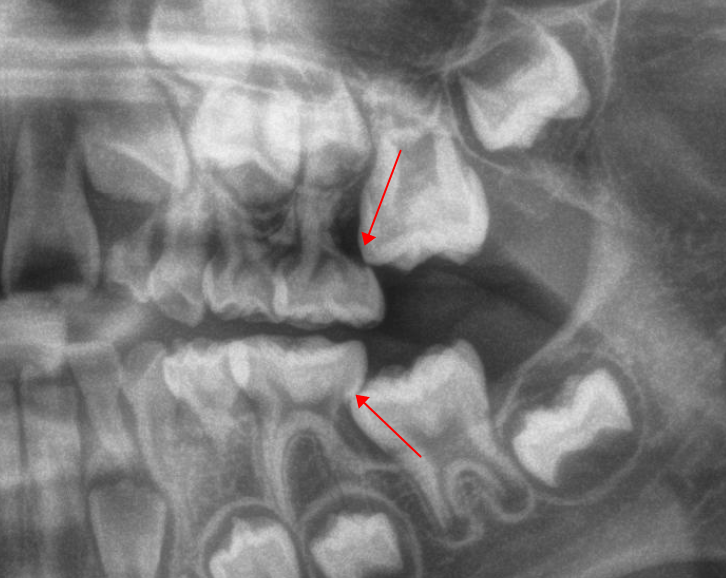

Q9.突然发现最里面长出了一颗牙,是智齿吗?

5-7岁的孩子发现最里面长牙,不是智齿,是六龄齿。

由于六龄齿的上方没有乳牙,因此它并不是等乳牙掉了才萌出,而是直接从牙床里萌出的,非常缺乏存在感,很容易被误认为是乳牙,但其实这4颗牙是要跟你一辈子,不会再换的恒牙。

曲面断层片怎么看换牙与身高有关吗?关于孩子换牙的所有疑问一篇说清_https://www.jmylbn.com_新闻资讯_第21张

划重点⚠️:六龄齿是恒牙,不会再换!

有时,六龄齿也会像智齿一样“顶在”前面的牙齿上而无法正常萌出,需要提前干预。因此,六龄齿萌出阶段也建议带孩子去医院检查一下。

划重点⚠️:六龄齿可能像智齿一样被“卡住”。

曲面断层片怎么看换牙与身高有关吗?关于孩子换牙的所有疑问一篇说清_https://www.jmylbn.com_新闻资讯_第22张

图注:六龄齿被“卡住”,无法正常萌出